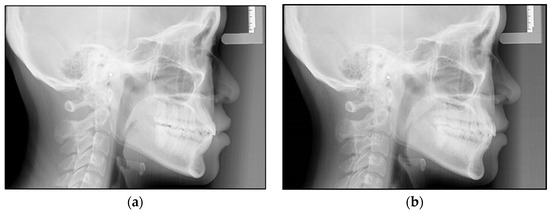

In total, 28 lateral cephalometric radiographs of the subjects were considered in this study. All the cephalometric radiographs were taken using a digital cephalometer (Orthopanmograph OP 200D, Instrumentarium Dental, Tuusula, Finland). The digital images were stored in a computer database with the manufacturer’s software and imported into Adobe Photoshop CS software (version 20). The software was used to resize the digital photos to a 1:1 ratio, and the images were printed using a 4800 dpi inkjet color printer (Canon PIXMA G4010, Canon Inc., Tokyo, Japan) on 180 gsm glossy inkjet photo paper made for high-quality photographic images. The cephalometric radiographs that were collected at the beginning were defined as Pretreatment (T0) and those at the end of the first series of Invisalign treatment were defined as Posttreatment (T1) (Figure 1a,b).

Figure 1. (a,b) Lateral cephalometric radiographs of a patient at the beginning of the treatment (a) and after treatment with the first series of Invisalign (b).